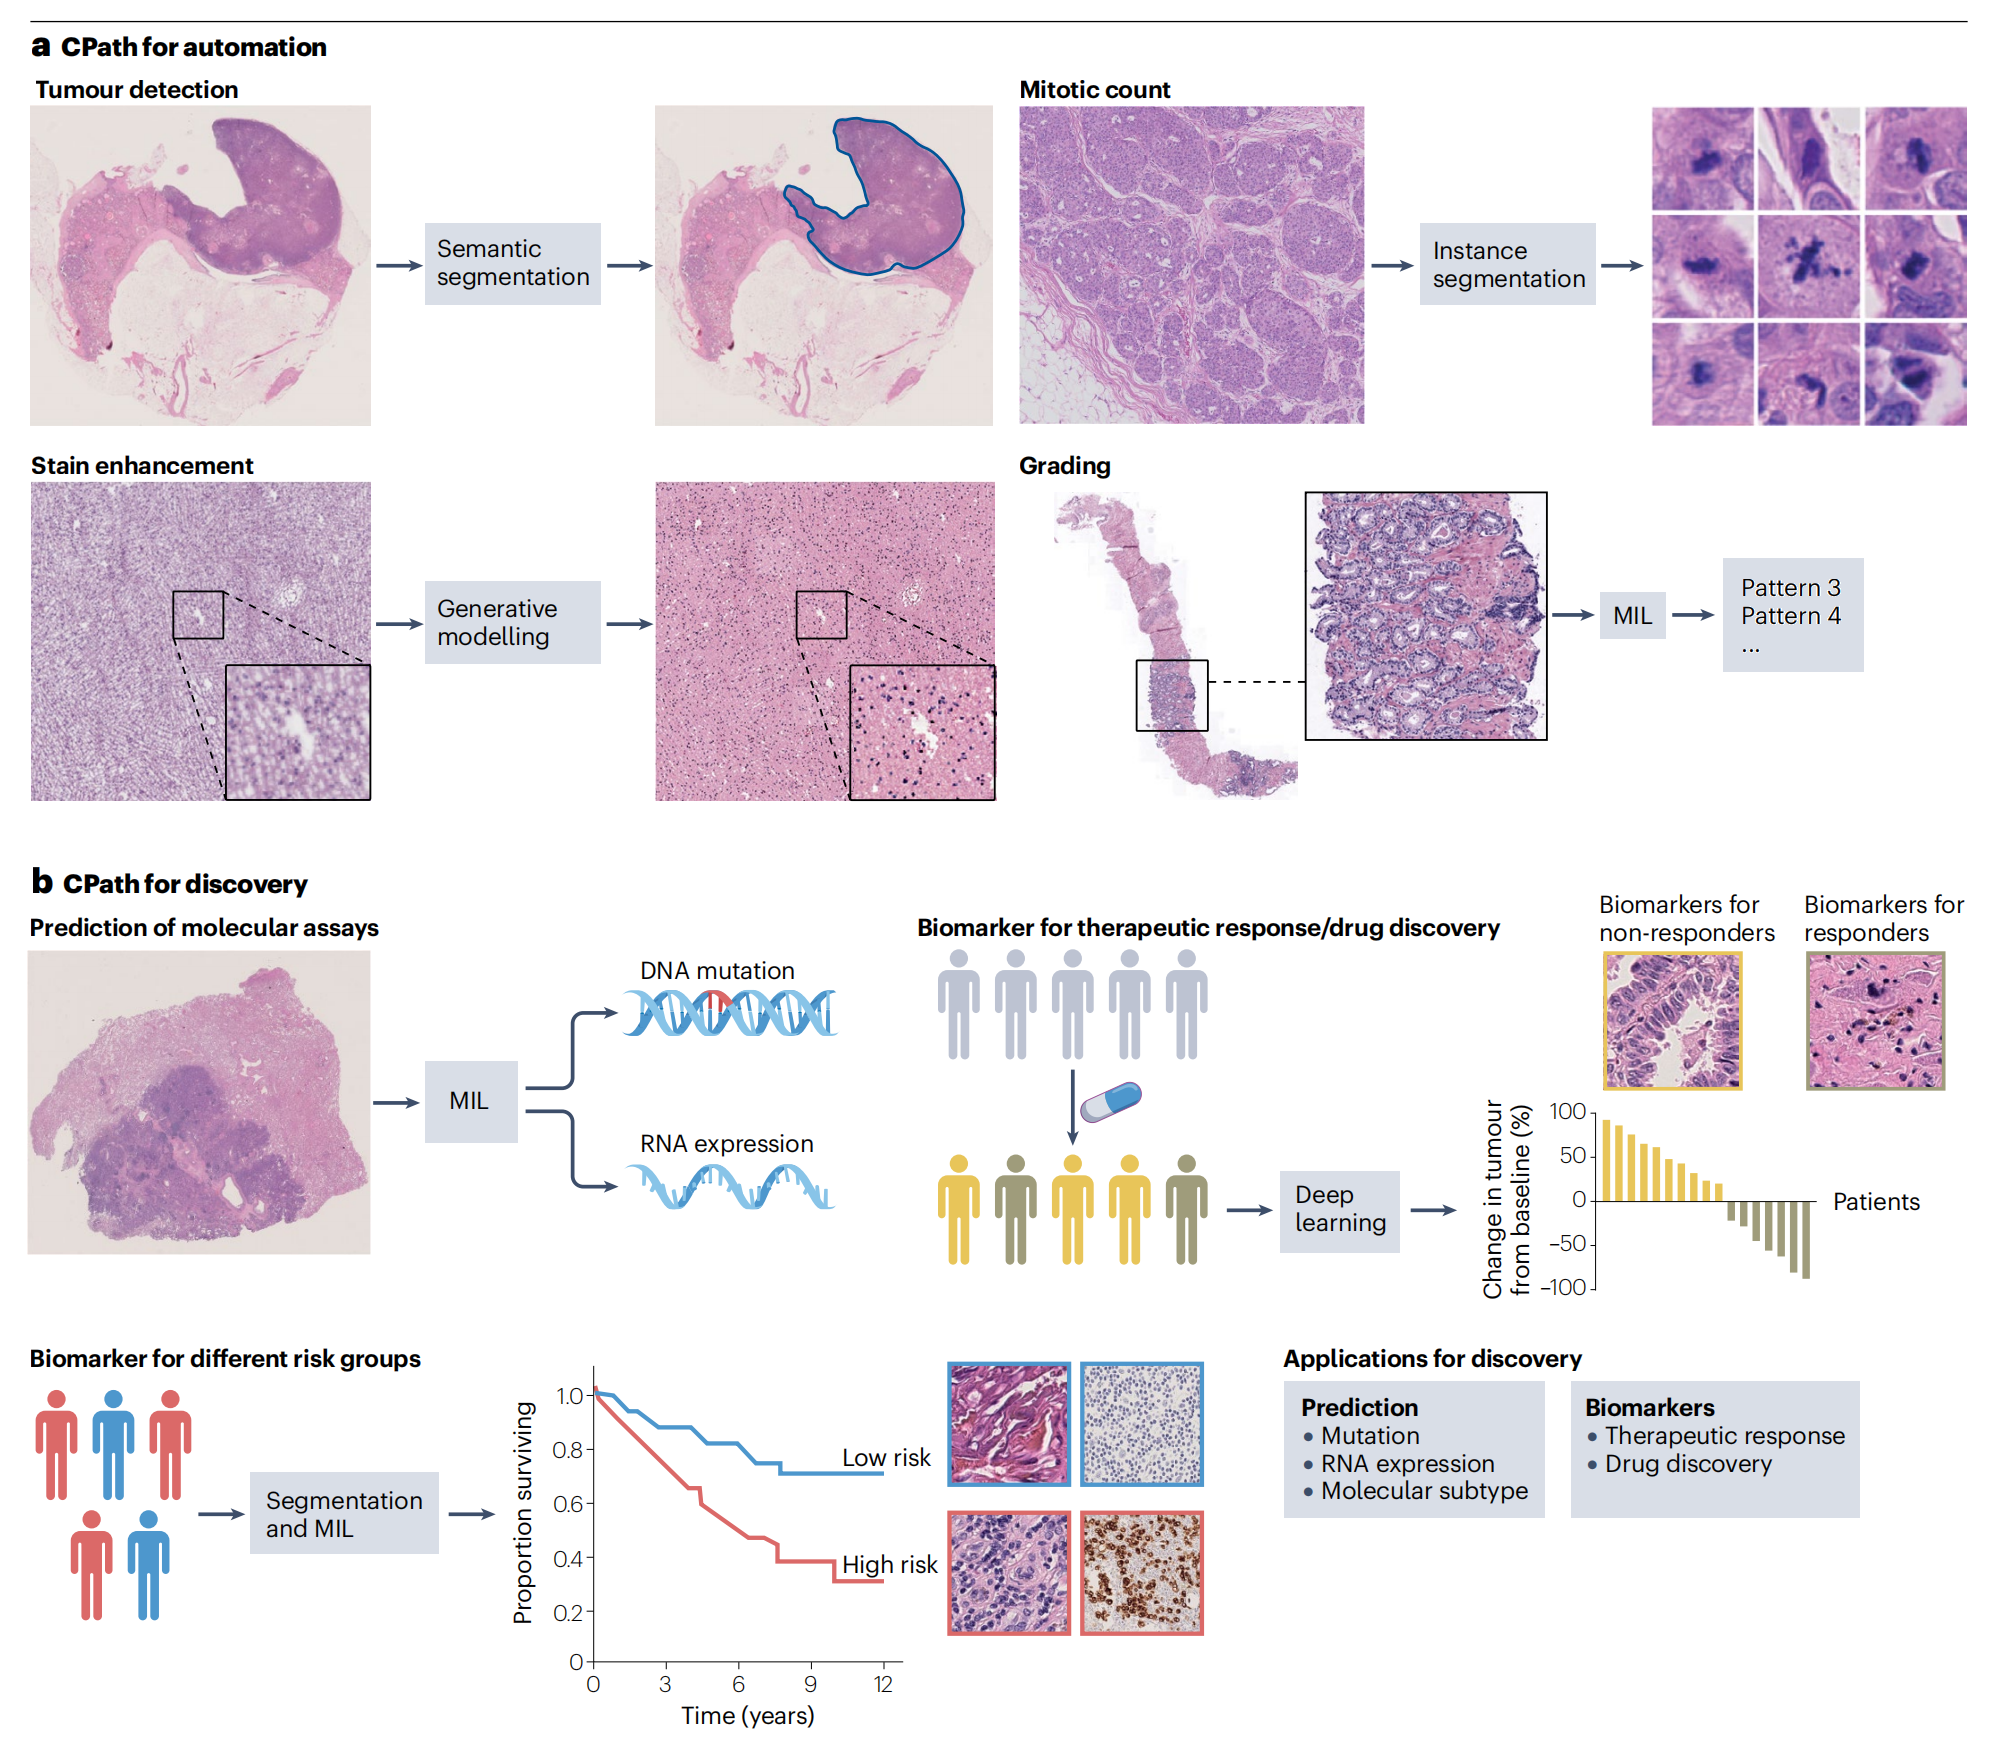

Fig. 4展示了计算病理学(CPath)如何整合到病理学中,其任务主要分为两大类:自动化现有的病理常规流程和指导生物医学研究。

这两类任务都依赖于全切片图像分类系统、基于人工智能的辅助工具(如分割网络),或两者的结合。

a部分强调了CPath在自动化方面的应用,它替代了病理学家日常繁重的手动工作,比如有丝分裂计数和癌症亚型分类任务,减轻了病理学家的负担并减少了观察者间的变异性。

b部分讨论了CPath在临床实践之外的应用,即作为生物医学研究的框架,例如发现与分子变化相关联的形态学特征和不同的风险/反应组。文中提到的MIL(多重实例学习)是一种机器学习方法,它在CPath中用于从整个切片图像中预测临床终点,如疾病诊断和分子变化。

简而言之,Fig. 4描述了CPath在提高病理学诊断效率和促进生物医学研究方面的双重作用。